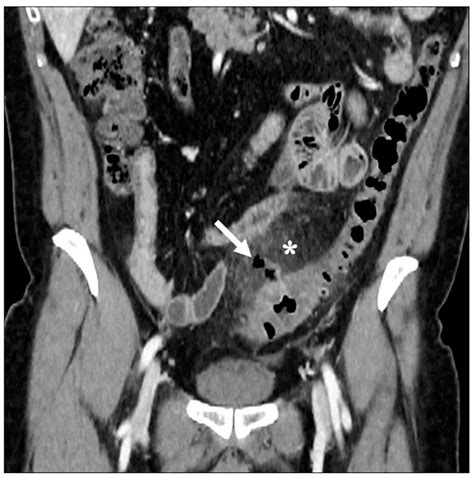

Diverticulitis is a painful condition that occurs when small pouches in the colon, known as diverticula, become inflamed or infected. When a patient presents with symptoms such as severe abdominal pain, fever, and changes in bowel habits, physicians must act quickly to make an accurate diagnosis. Among the various diagnostic tools available in modern medicine, a CT scan for diverticulitis is considered the gold standard. Its ability to provide detailed, cross-sectional images of the abdomen allows healthcare providers to confirm the presence of inflammation, assess the severity of the condition, and rule out other potential causes of abdominal distress.

Once the scan is completed, a radiologist will interpret the images and generate a report. If the scan confirms a diagnosis of diverticulitis, the radiologist will often grade the severity of the disease. This grading system is crucial for determining the appropriate course of treatment. The results of your CT scan for diverticulitis will likely focus on several key indicators:

• Wall Thickening: The degree to which the colon wall has thickened due to inflammation.

• Fat Stranding: A hazy appearance in the fat surrounding the colon, which is a classic sign of localized inflammation.

• Presence of Abscesses: Whether there are pockets of pus that may require drainage or specific antibiotic therapy.

• Free Air: A critical finding that may indicate a perforation, which is a medical emergency requiring immediate surgical consultation.